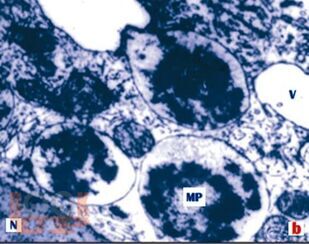

Сборник микро- и макропрепаратов по дисциплине «Основы патологии»

Сборник микро- и макропрепаратов по дисциплине подготовлен сотрудниками кафедры патофизиологии ФГБОУ ВО РязГМУ Минздрава России и предназначено для организации аудиторной и внеаудиторной работы студентов, обучающихся по программе среднего профессионального образования по специальностям 34.02.01 Сестринское дело (СПО) и 31.02.01 Лечебное дело (СПО).